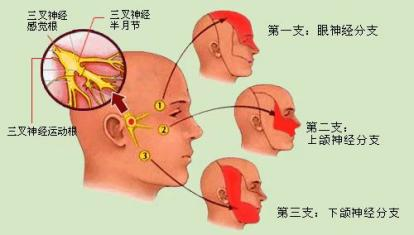

什么是三叉神经痛?

三叉神经痛又称“天下第一痛”,主要以单侧头面部反复发作、短暂性、电击样、烧灼样、刀割样等疼痛为特点,突发突止,一般历时几秒到数分钟,通常说话、咀嚼、洗脸、刷牙、吹风等时可诱发,常常累及三叉神经一个或多个分支。严重影响患者生活质量。具体病因目前不清楚,考虑:1.和神经伴行动脉血管关系太近,动脉搏动刺激神经,诱发疼痛。2.考虑神经自身病变引起。

经过面部口角处穿刺到三叉神经半月节内,放入球囊,向球囊里打入对比剂,使球囊扩张,完美显示一个“梨”形,压迫3-5分钟,压迫毁损感觉神经,保留运动神经,阻断疼痛信号传导,达到止痛目的。适合单支或多支发病患者,尤其高龄、合并症多,不愿意接受开颅手术患者。术后面部稍有麻木。